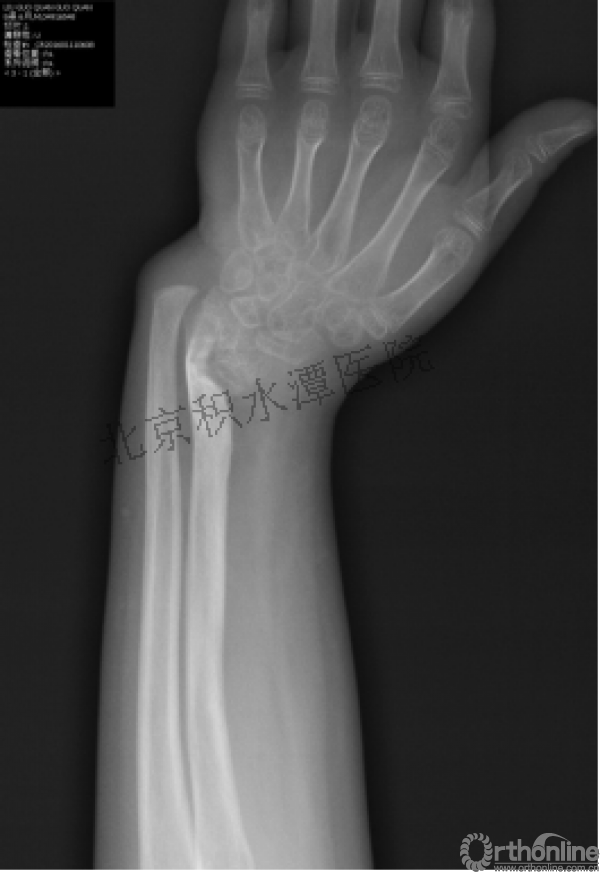

病例分享六

7岁、男孩,桡骨远端骨折

原始损伤片

手法整复后 - 45分钟!

伤后4天复查

伤后30天!

医生的处理方法!——医生终于没有坚持自己的原则!

伤后40天—切开复位内固定!

伤后18个月

如何面对?

心情之压抑无以言表!

手术历时近 5小时!心情之压抑无以言表!因为当时的经治医生是他们的进修生!感觉是他们的失职甚至渎职!

唯一可以肯定—预后不佳!郭教授是党员!是无神论者!但是很诡异的事情:手术中发生—C形臂看不清!拍片条件总是调节不好!手术器械换了三套!内固定钢板总不合适!

术后15月,虽然家长满意了,但是他们医生不满意!